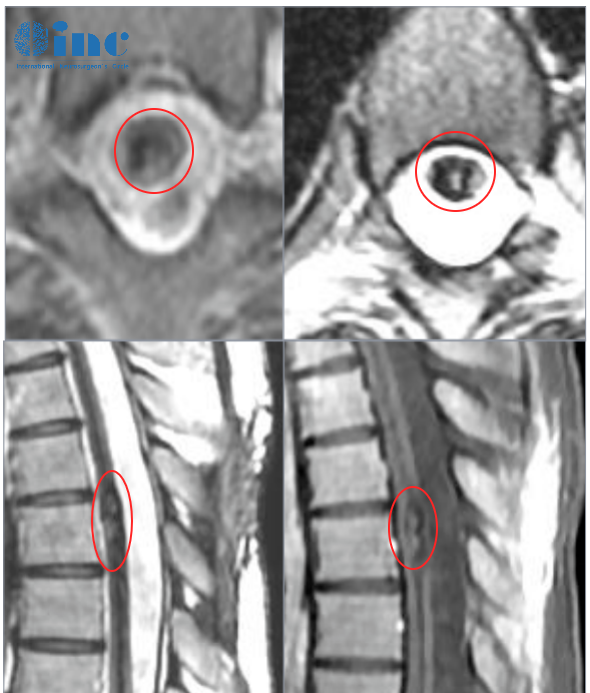

- 文章標(biāo)題:胸髓髓內(nèi)海綿狀血管瘤:手術(shù)主要目標(biāo)是切除殘留的血管畸形,以免再次出血!